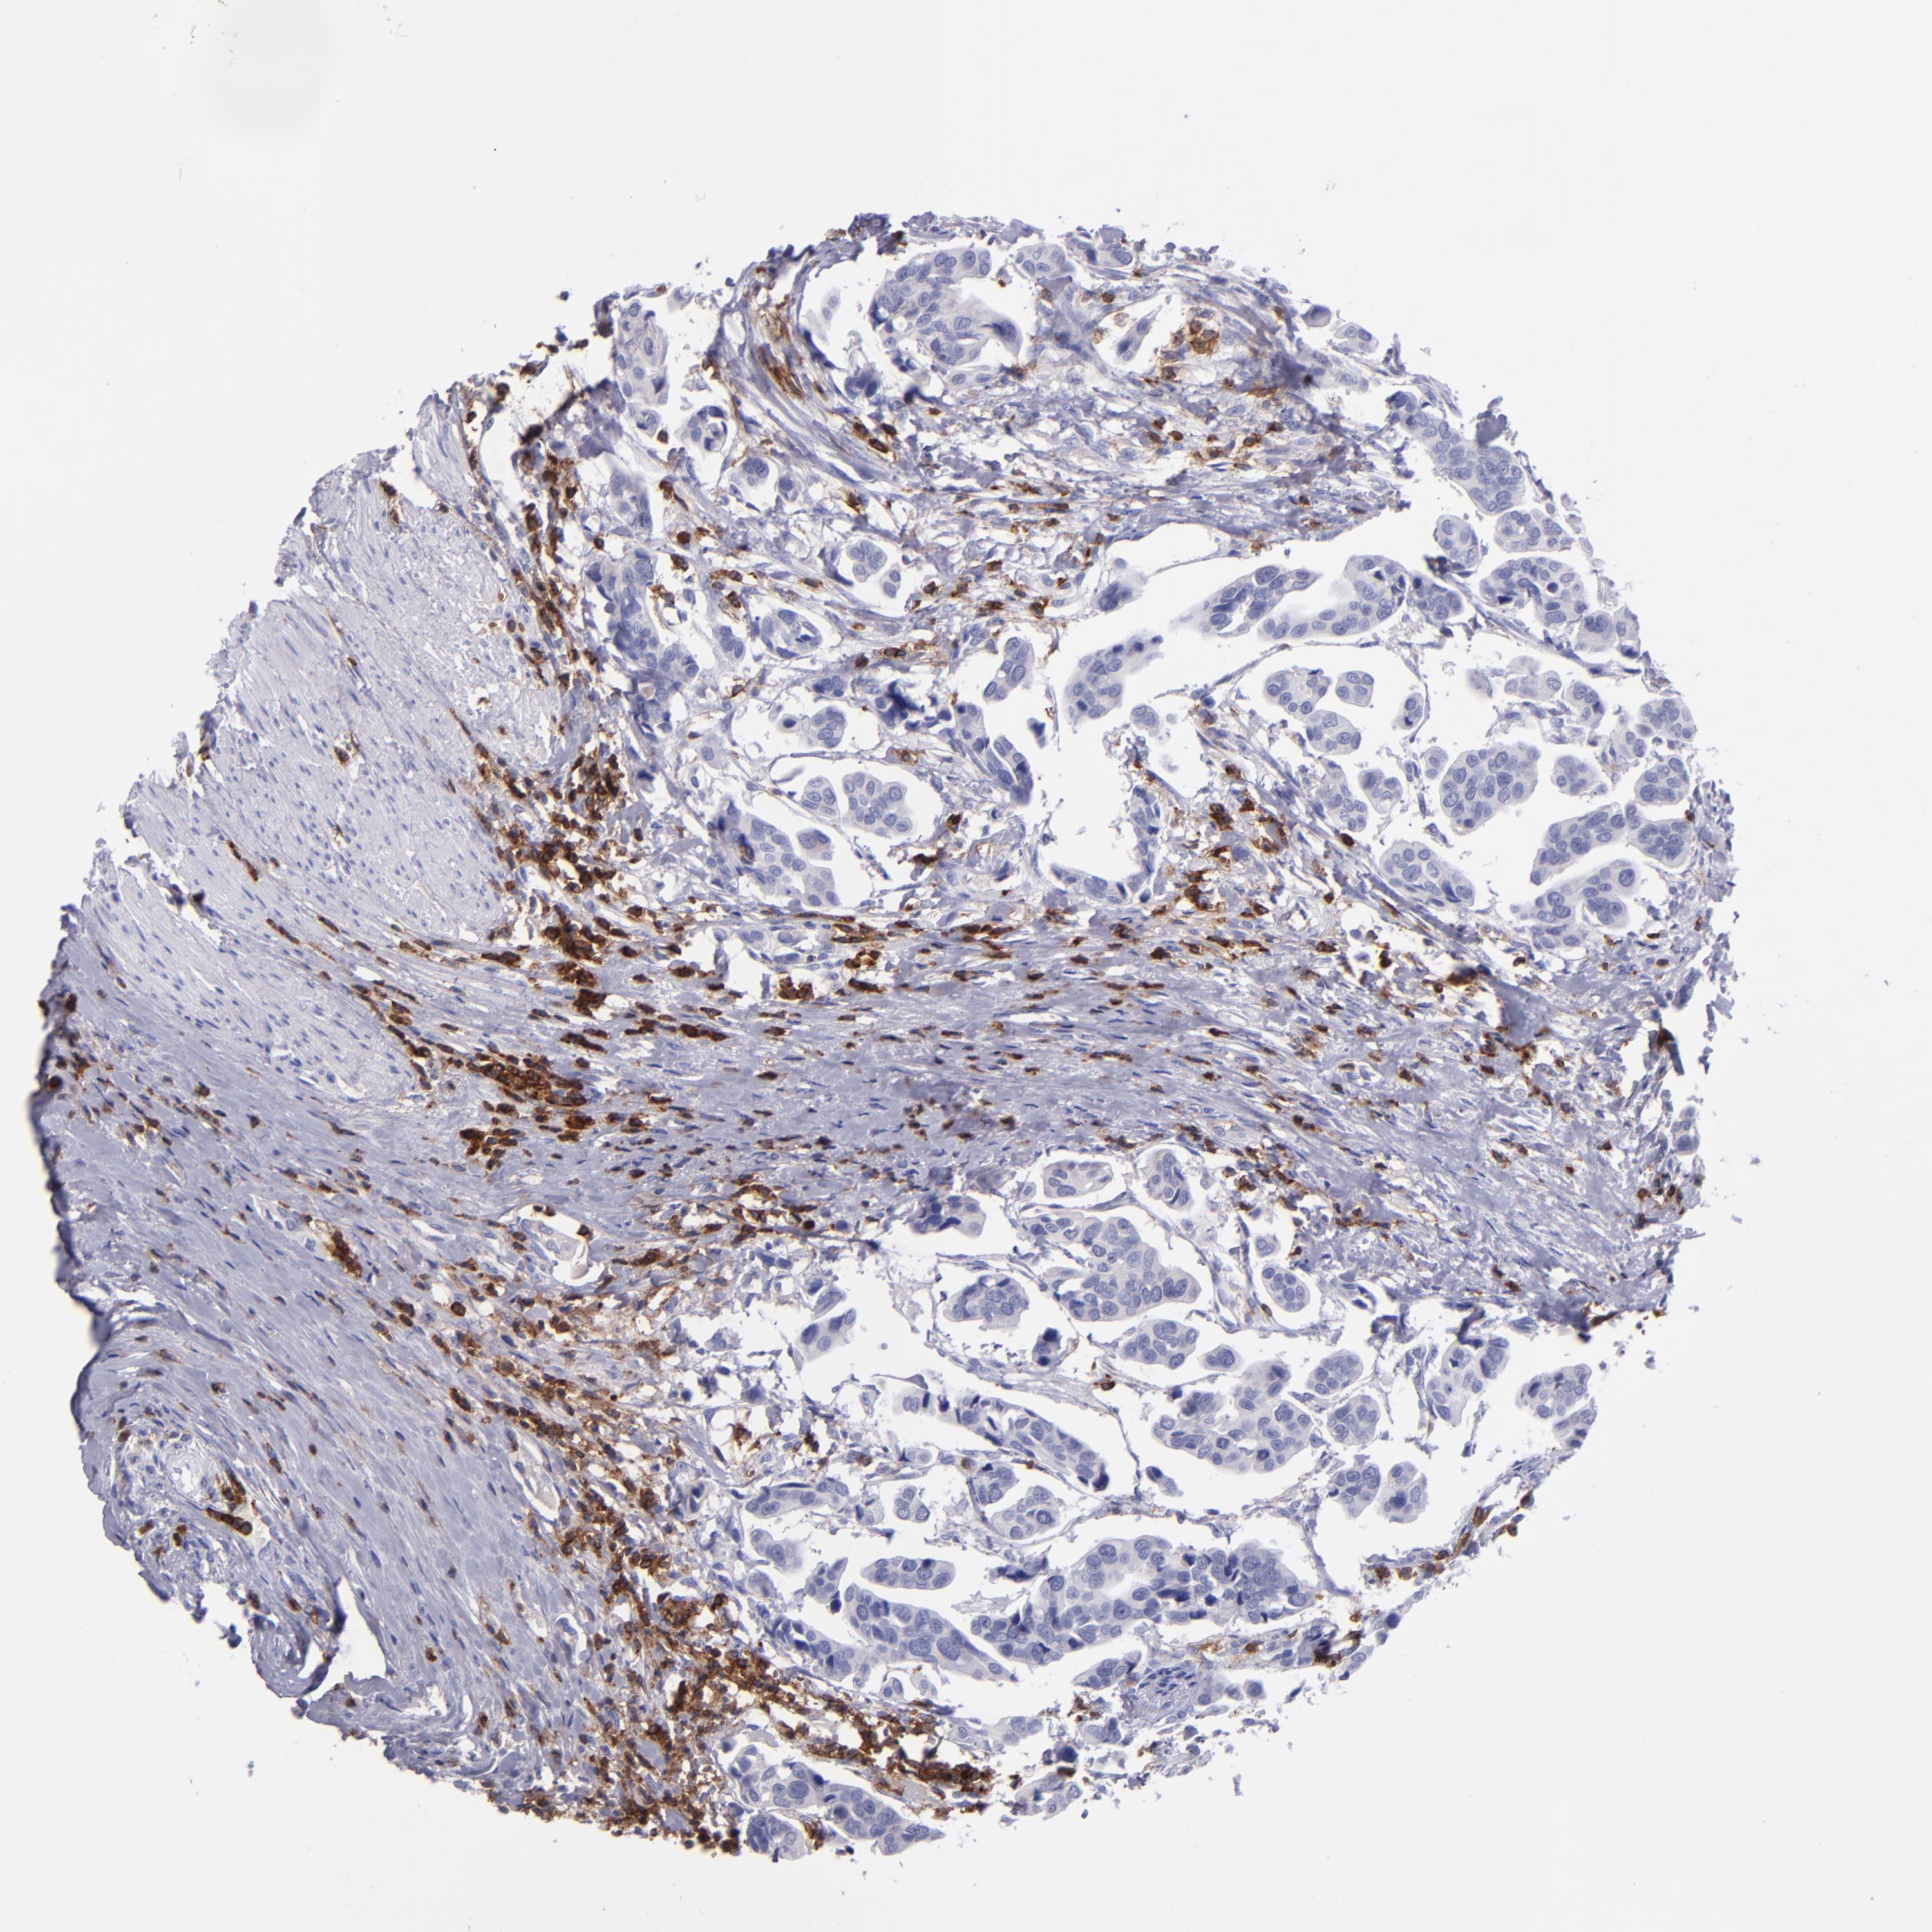

UROTHELIAL CANCER - Protein expressioni

A mouse-over function shows sample information and annotation data. Click on an image to view it in a full screen mode. Samples can be filtered based on level of antibody staining by selecting one or several of the following categories: high, medium, low and not detected. The assay and annotation is described here.

Note that samples used for immunohistochemistry by the Human Protein Atlas do not correspond to samples in the TCGA dataset.

Antibody stainingi

Antibody staining in the annotated cell types in the current human tissue is reported as not detected, low, medium, or high, based on conventional immunohistochemistry profiling in selected tissues. This score is based on the combination of the staining intensity and fraction of stained cells.

Each image is clickable and will lead to virtual microscopy that enables deeper exploration of all samples and also displays staining intensity scores, fraction scores and subcellular localization as well as patient and tissue information for each sample.

Antibody CAB002498

Staining

High

Medium

Low

Not detected

Intensity

Strong

Moderate

Weak

Negative

Quantity

>75%

75%-25%

<25%

None

Location

Nuclear

Cytoplasmic/membranous

Cytoplasmic/membranous,nuclear

Urothelial carcinoma, High grade

Urothelial carcinoma, Low grade

Adenocarcinoma, NOS